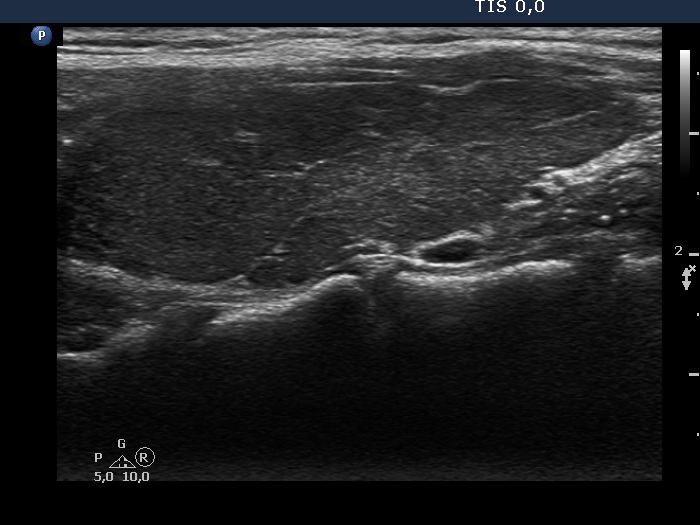

Right lobe, transverse scan

Right lobe, longitudinal scan

Left lobe, transverse scan

Left lobe, longitudinal scan

Ultrasonography. The thyroid was echonormal and presented moderately hypoechoic areas. The echogenicity index was around 15%. The vascularity was decreased.